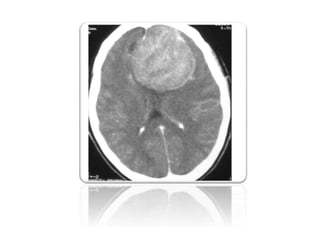

Computerized Tomography

CT is often the first modality employed to investigate

neurological signs or symptoms, and often is the modality

which detects an incidental lesion.

• 60% slightly hyper-dense to normal brain

• 20-30% have some calcification 8

• 72% brightly and homogenously contrast enhance 8, less frequent in

malignant or cystic variants

• Hyperostosis

otypical for meningiomas that abut the base of skull

oneed to distinguish reactive hyperostosis from skull vault invasion (eventually

involves the outer table too)

Lytic regions

The scans below show a patient with meningioma

The scans below show the same patient with meningioma SIX

The scans belowshow a patient with meningioma The scans below show the same patient with meningioma SIX MONTHS after gamma knife treatment.